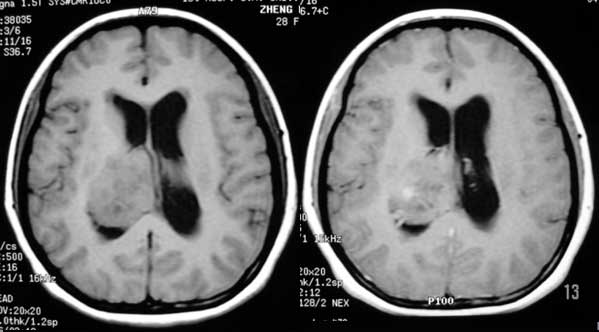

女性,28岁。头痛请会诊

右侧丘脑类圆形等t1,长t2病灶,t1增强明显强化。

女性,28岁。头痛请会诊。

考虑:①丘脑胶质瘤可能大。②脑积水。

t1等信号内出现点状高信号,考虑为出血灶,肿块内侧可见弧形低信号,为脑积液影。长t2,其内有混杂信号,周壁强化明显,内不规则强化,生长位置似在右侧丘脑,又似在来源于侧脑室,故脉络丛乳头状瘤不排外。